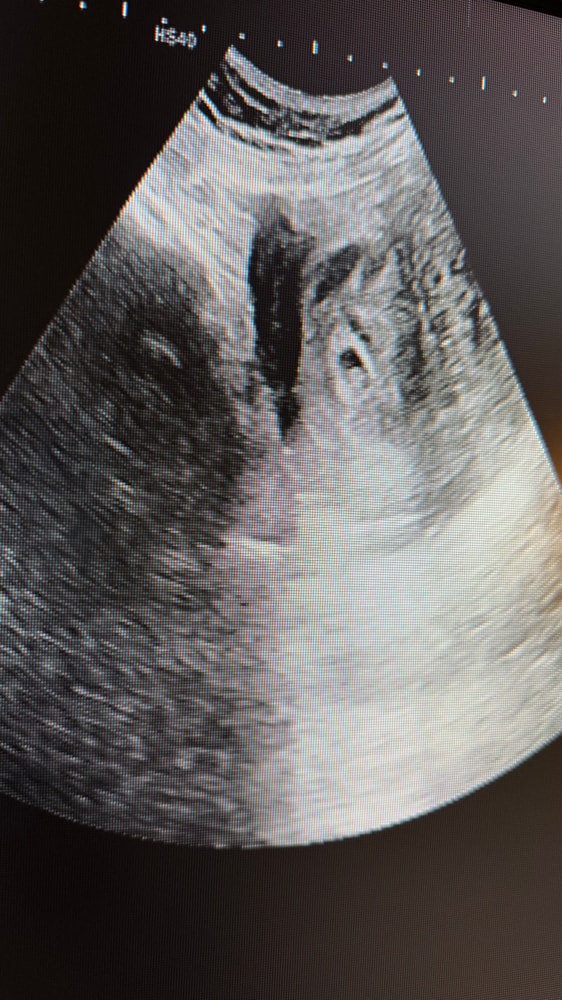

Жёлтое тело здесь не главное,у вас пя 8,4,а эмбрион 8,6,т.е они одного размера и жм у вас уже нет,но сердцебиение при этом есть, очень странное УЗИ

Переделайте УЗИ,это очень странное какое -то вообще пя у вас меньше чем эмбрион,хотя эмбрион находится внутри пя,а фото есть с УЗИ со снимком ?

AFINA , к сожалению да,пя маленькое и эмбрион с размером пя,ему развиваться некуда уже,у вас в заключении написано не про жёлтое тело,а про несоответствие размеров плодного яйца,оно у вас маленькое и это плохо

AFINA , да,но для благополучной беременности в пя место должно быть, минимальная разница 5 мм между пя и ктр и она должна сохраняться,у вас вообще разницы нет,они одинаковые,пя задавит эмбрион,с вашим эмбрионом 8,6 пя должно минимум быть 14 мм хотя бы

AFINA , с такими данными да,к сожалению шансов нет,странно что ещё живой,сколько наблюдала с разницей в 1-2 мм с пя уже замирали,у вас ещё возможно ошиблись в замерах,так как немного УЗИ странноватое, поэтому не буду делать прогнозов,может у вас и пя нормальное,смотря ещё с какого ракурса фоткали

AFINA , переделайте,меня это узи все равно смущает из-за того что жм нет,но это питание эмбриона и он по-любому должен быть,темболие если у эмбриона сердцебиение есть,может там меняли абы-как